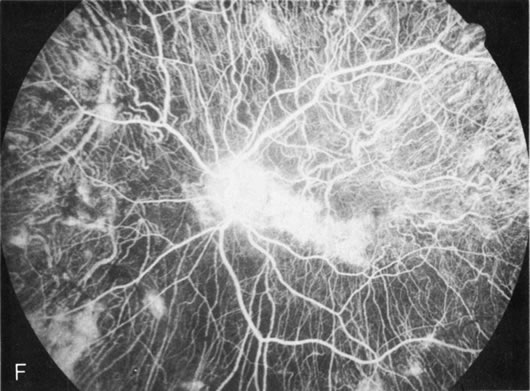

Generalized choroidal dystrophy is usually noted in middle-aged mildly symptomatic individuals who show a predominantly peripapillary or pericentral distribution of choroidal atrophy. Gradually, over the years these areas enlarge to eventually involve the entire retina. These changes are vividly seen on FA (Fig. 6).

Fig. 6. Generalized choroidal dystrophy. This 65-year-old woman gradually developed enlarging, progressive areas of choroidal atrophy over a 20-year period. When initially seen, the abnormalities were confined to the peripapillary and macular region (A,B). In a recent examination, the generalized choroidal atrophy is vividly demonstrated on angiography (C–F).